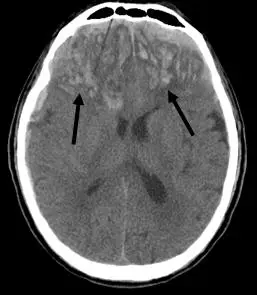

頭部外傷的病人, CT 影像如下圖,箭號所指的是:

本題 CT 影像為非強化(plain)頭部 CT,可見以下特徵:

- 病灶位置:兩側大腦半球前部(雙側額葉、顳葉交界區)有多處高密度病灶,箭號分別指向左側與右側的病灶。病灶位於腦實質內部,而非顱骨內板與硬腦膜之間,也非硬腦膜下腔。

- 病灶形態:影像顯示病灶呈斑塊狀、不規則形,並非鏡頭形(lenticular/biconvex)或月牙形(crescentic),這一點非常重要。

- 密度特徵:病灶呈高密度(hyperdense),代表急性出血,與周圍較低密度的腦實質形成對比。

- 分布特點:雙側前顳葉/下額葉是腦挫傷最常見的好發部位,因顱骨底部粗糙骨面(蝶骨嵴、顳骨岩部)的剪切力所致,符合典型的 coup-contrecoup(衝擊-對衝) 機制。